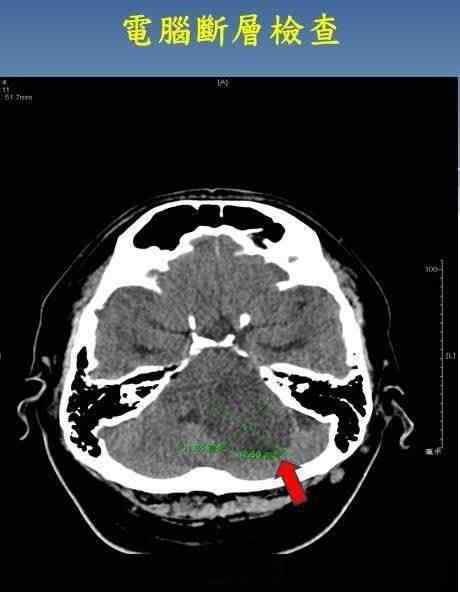

43岁男性,左上颚牙疼了几个月,拔除龋齿后没有好转。转到神经内科进行三叉神经和脑干神经回路传导和计算机断层检查后,发现脑干内近5 cm的肿瘤压迫了三叉神经。及时安排了手术切除,不仅救了他的命,而且牙痛也完全消失了。

病人接受了计算机断层扫描检查,发现脑干有肿瘤。